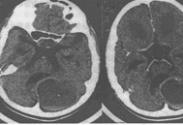

血管網狀細胞瘤為良性腫瘤,起源于中胚葉細胞的胚胎殘余組織,為顱內真性血管性的腫瘤,多發生在小腦。